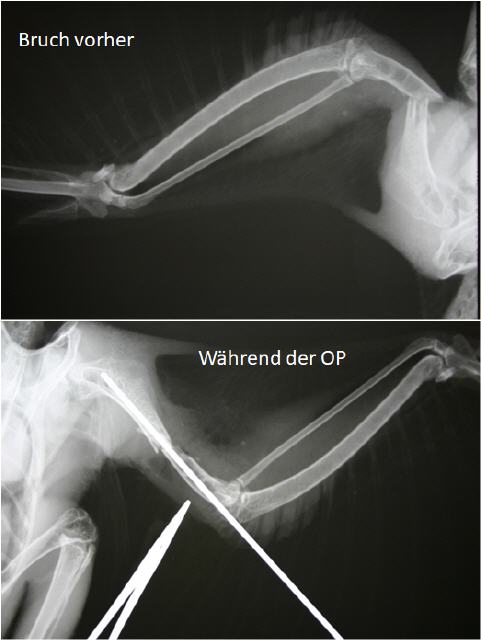

Geglückte OP bei Stockente

Die Stockente wurde nach einem Zusammenstoß mit einem Auto aufgesammelt und zu einer Vogelfreundin gebracht. Diese ist eine langjährige Kundin von mir und weiß, dass ich ebenfalls ein großer Vogelliebhaber bin. Die Vogelfreundin unterstützt die Praxis seit vielen Jahren bei der Pflege und Auswilderung von Wildvögeln, für sie kam eine Euthanasie nicht infrage. Ich sollte versuchen, den Ruderfuß der Ente zu retten, was glücklicher Weise auch gelang. Wir hoffen nun, dass sich die Stockente rasch erholt.